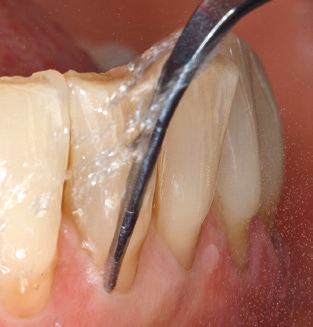

Fig. 4: Flexible probes with millimetre markings are recommended for the probing of dental implants (e.g. Colorvue Kit PCV11KIT6, Hu­Friedy). – Fig. 5a and b: A straight working tip (1P, W&H Dentalwerk Bürmoos GmbH) is a suitable instrument for use on all natural teeth. – Fig. 6: Curved working tips (3Pr/3Pl, W&H Dentalwerk Bürmoos GmbH) lend themselves to the processing of difficult-to-reach areas of the tooth and root surfaces (e.g. furcations). – Fig. 7: The tapered, hexagonal implant cleaning tip (1I, W&H Dentalwerk Bürmoos GmbH) permits atraumatic and efficient cleaning of the crown and abutment surfaces. – Fig. 8: Titanium and carbon curettes are suitable instruments for the manual cleaning of the implant surfaces.

Following machine cleaning of the tooth and implant surfaces, the surfaces of the natural teeth are cleaned manually using standard hand instruments. When performing manual cleaning, particular attention must be given to maintaining the correct angle of application, appropriate sharpness, good support and working with the curette from apical to coronal. Either titanium or carbon curettes should be used for post-cleaning of the implant structures (Fig. 8). In addition to the use of ultrasonic devices, power jet devices can also be used in conservative dentistry. However, it must be taken into consideration that these procedures are not suitable for removing hard deposits and thus they cannot replace the use of hand instruments and ultrasonic instruments completely. In all cases, cleaning is followed by mechanical polishing of the accessible tooth and implant surfaces with polishing cups and polishing compounds (Fig. 9).